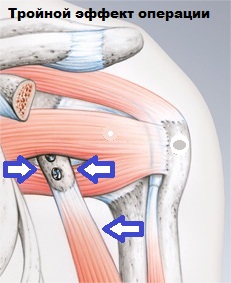

Подобная манипуляция восполняет недостающую кость в данной зоне. Процедура имеет высокий успех, что связано с тройным эффектом операции.

1. Перенесенный клювовидный отросток восстанавливает и увеличивает площадь суставной впадины

2. Мышца и сухожилие, находящиеся на клювовидном отростке, дополнительно стабилизирует сустав, когда рука отведена и ротирована снаружи (эффект гамака).

3. В результате операции возможно выполнить пластику капсулы.

В мировой медицине эта операция носит название - Операция Латарже (Latarjet - Bristow) и является наиболее часто используемой при данном виде повреждений.